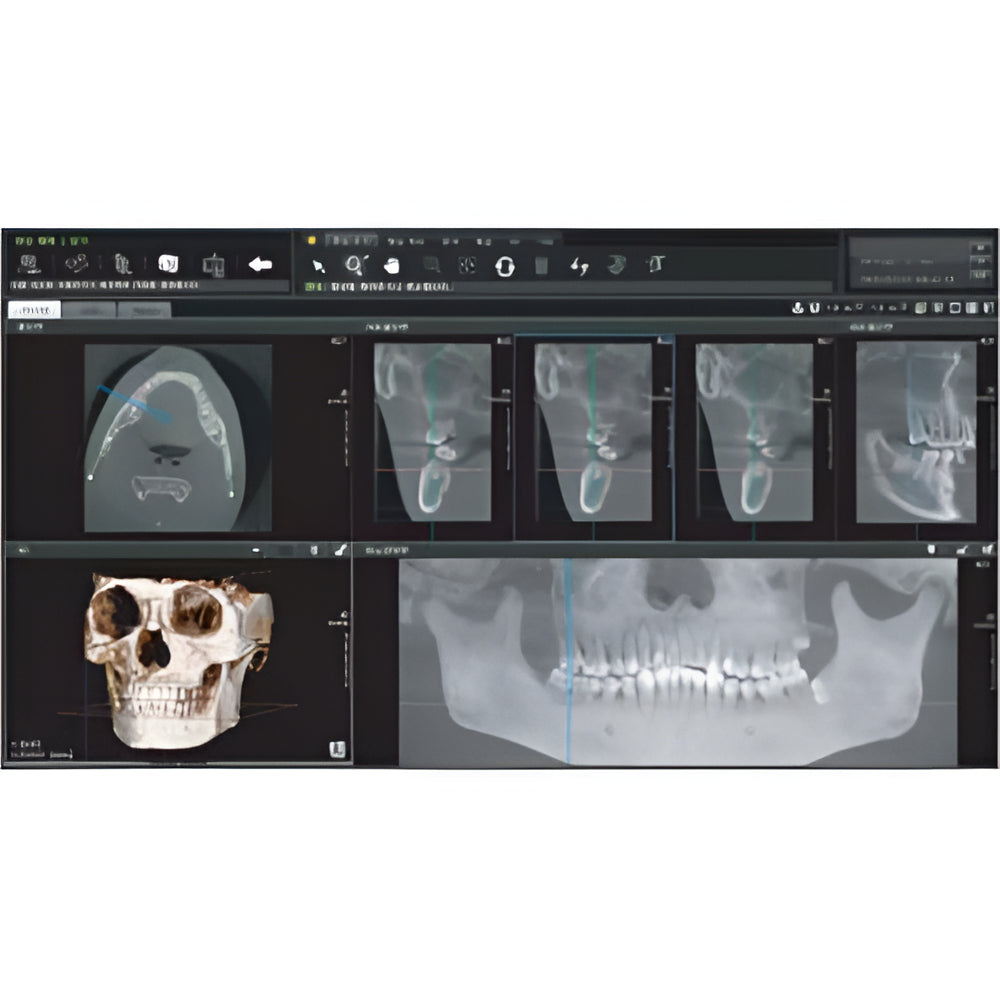

Genoray Papaya Plus Pan + CBCT (14x14 FOV)

Genoray Papaya Plus Pan + CBCT (14x14 FOV)

Papaya uses the CdTe sensor, which improves image quality while keeping radiation exposure to a minimum. The CdTe (Cadimium telluride) sensor overcomes the limitations of a CMOS sensor to always produce high quality images.

- 3D imaging software

- Field Of View: 4x5, 7x7, 8x8, 14x8, 14x14